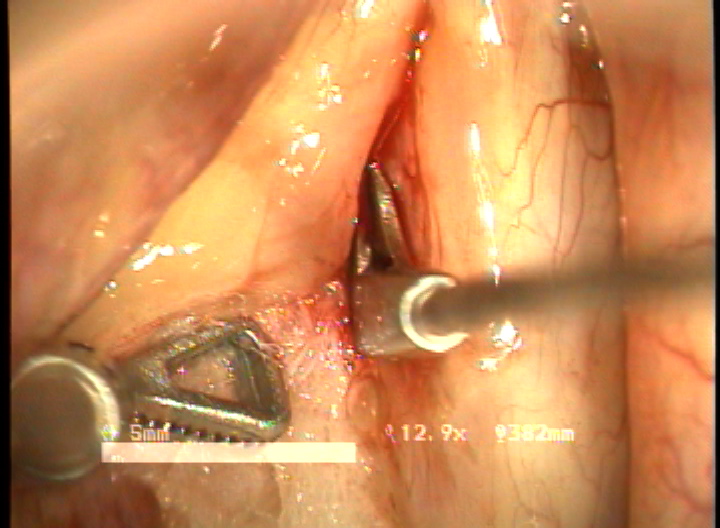

목적 : 전성문횡격막(anterior glottic web)은 선천성이나 수술과 같은 이차적인 원인에 의해서 발생되는 난치성 후두질환이다. 또한 기존의 치료방법으로는 음성개선의 효과가 매우 낮은 결과를 얻고 있다. 이에 음성의 보존과 함께 일차적 시술로서 치료가 가능한 double rotation microflap 을 이용한 새로운 술식을 보고하며, 이술식의 치료결과와 음성학적 개선을 알아보고자 하였다.

방법 : 2006년 1월 부터 2007년 12월 까지 예송이비인후과에서 전성문횡격막으로 진단되어 double rotational microflap laryngoplasty를 시행받고 1년간 장기추적이 가능하였던 6명의 환자를 대상으로 후향적 분석을 시행하였다. 원인적인 요인과 동반질환으로는 후두유두종 술후 합병증 4례, 후두외상 1례, 폴립양성대 1례 였다. 남녀 각각 3례였으며, 평균연령은 39세 였다. 추적기간은 21.5 개월이었다. 술 후 2개월과 6개월에 음성개선에 대한 주관적인 음성평가를 시행하였으며, 음성분석검사와 후두스트로보스코피 검사를 통하여 객관적인 음성평가와 성대점막파동의 변화를 관찰하였다. 통계적 유의성은 Wilcoxon Signed Ranks Test로 검정하였다.

결과 : 음성개선에 대한 주관적인 평가로서 수술전 Voice Handicap Index는 평균 19.7 에서 술후 11.5로 감소하였다. 공기역학적인검사상 성문하압은 5.5에서 4.5로 감소되었으며, 최대발성시간 13.7에서 16.1로 증가되었다. 음성분석검사상 sPPQ, sAPQ, NHR, SPI, DSH가 모두 통계학적으로 유의하게 감소하였다. 후두스토로보스코피검사상 모든 례에서 재발의 징후없이 성대점막파동의 의미있는 호전이 나타났다. 합병증으로 1례에서 염증성 육아종형성이 관찰되었으나 미세피판의 괴사나 탈락은 관찰되지 않았다.

결론 : 전성문횡격막의 새로운 수술방법으로서 double rotational microflap laryngoplasty는 일차수술로 만족스러운 음성학적 치료결과를 얻을 수 있는 매우 유용한 술식이라 사료된다.